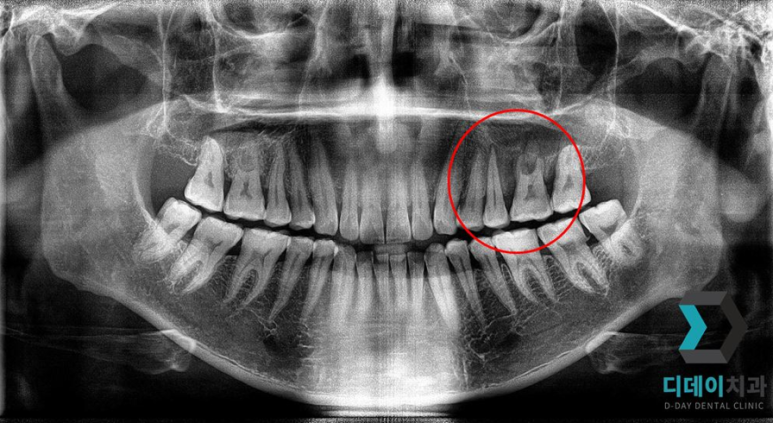

<전 2021-12-28>

<후 2022-08-06>